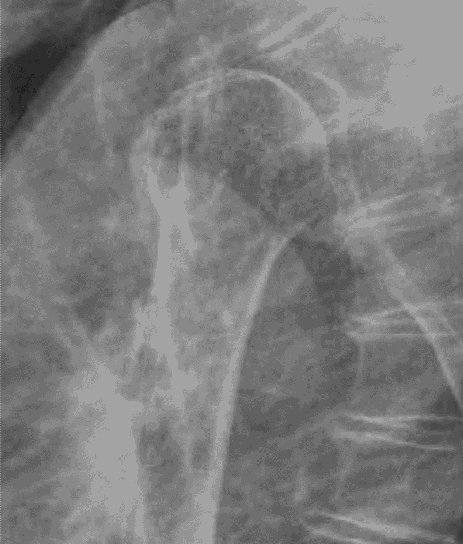

Depending on preference, the surgeon can choose from multiple types of the Reverse Glenoid Baseplates. Thanks to its elaborated design it can host a central Bone Screw and up to 4 peripheral Bone Screws. The surgeon can select from angle-stable (locking), polyaxial angle-stable (locking) and standard screw fixation with cortical and cancellous thread design.1 All standard Glenoid implants are designed with a curved back side resulting in bone sparing preparation and better fixation.7 Wedged and lateralizing Baseplates with diAerent oAsets and angulations as well as long pegged Baseplates are suitable for glenoid reconstruction to address glenoid defects and glenoid bone loss.3